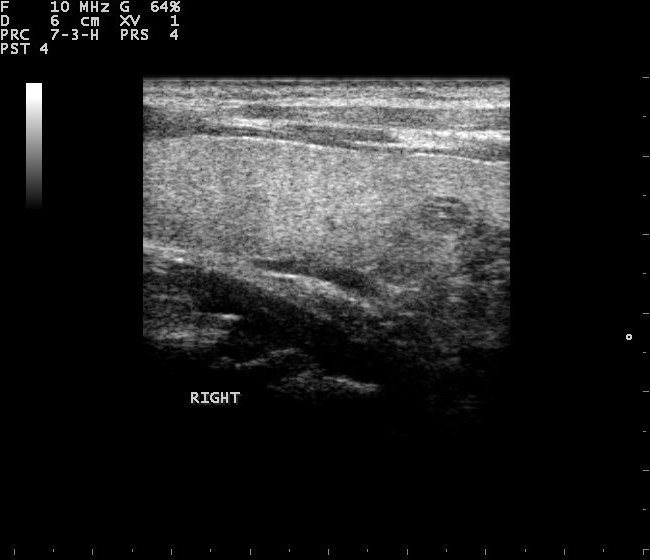

Thyroid phantom for ultrasound and nuclear medicine imaging